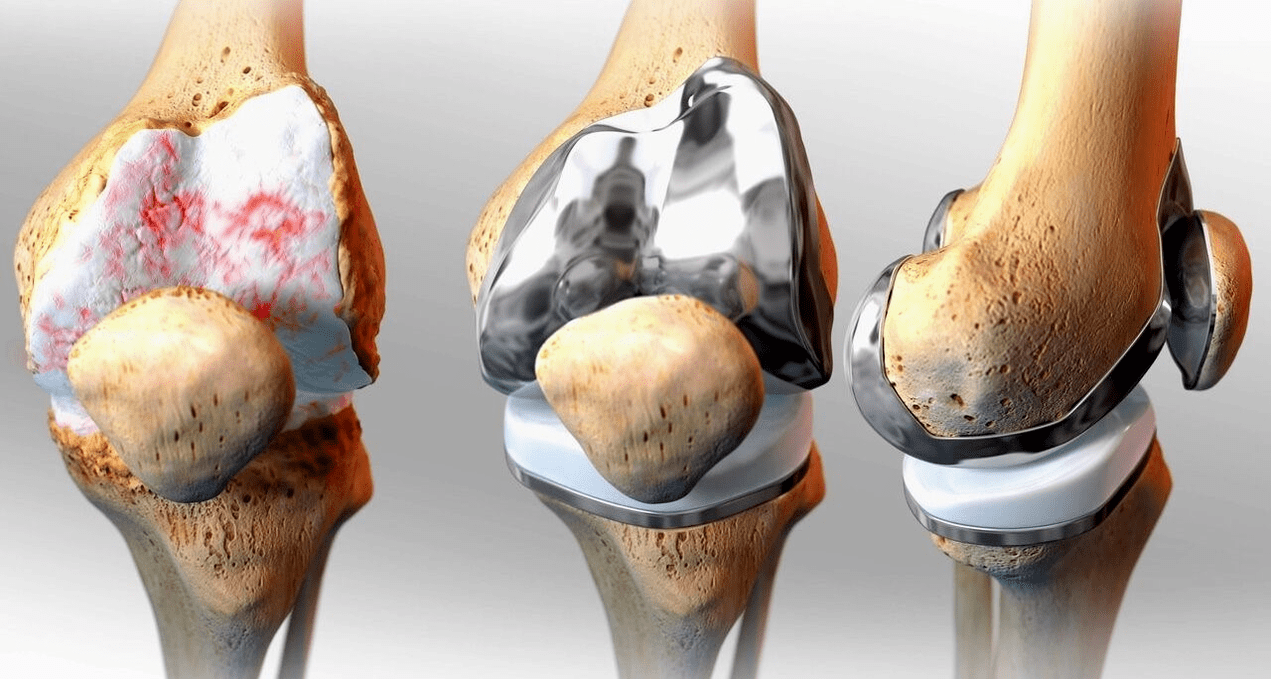

Surgical treatment and endoprosthesis.

Stent replacement is a common and effective surgical method for the treatment of severe gonarthrosis, maintaining limb mobility and the ability to lead a full life afterwards.It is a high-tech operation that lasts approximately an hour and a half.In the postoperative period, prolonged rehabilitation and development of the joint is necessary.After 25 to 30 years, when the artificial joint wears out, it needs to be replaced again.

Surgical — arthroscopy (a low-traumatic method to treat intra-articular pathologies and eliminate damaged structures), endoprostheses.